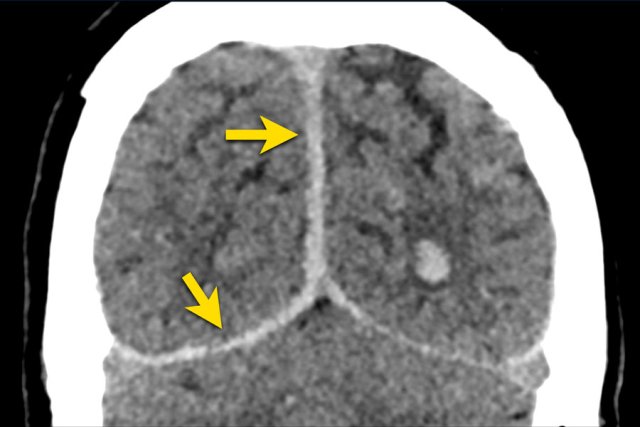

A 46 year-old man had a high energy trauma with his motorcycle.

The initial EMV score was 2-5-3 and his pupils were non-reactive and dilated.

CT findings

• Petechial hemorrhages in both frontal lobes.

• Bilateral Le Fort II fractures.

MRI was requested because of persisting cognitive deficits.

MRI findings

• Extensive (stage 3) diffuse axonal injury (DAI)

• Involvement of the subcortical areas, the corpus callosum, the right thalamus and putamen, the brain stem, the cerebellar peduncles and the right cerebellar hemisphere.

• Mild global atrophy.